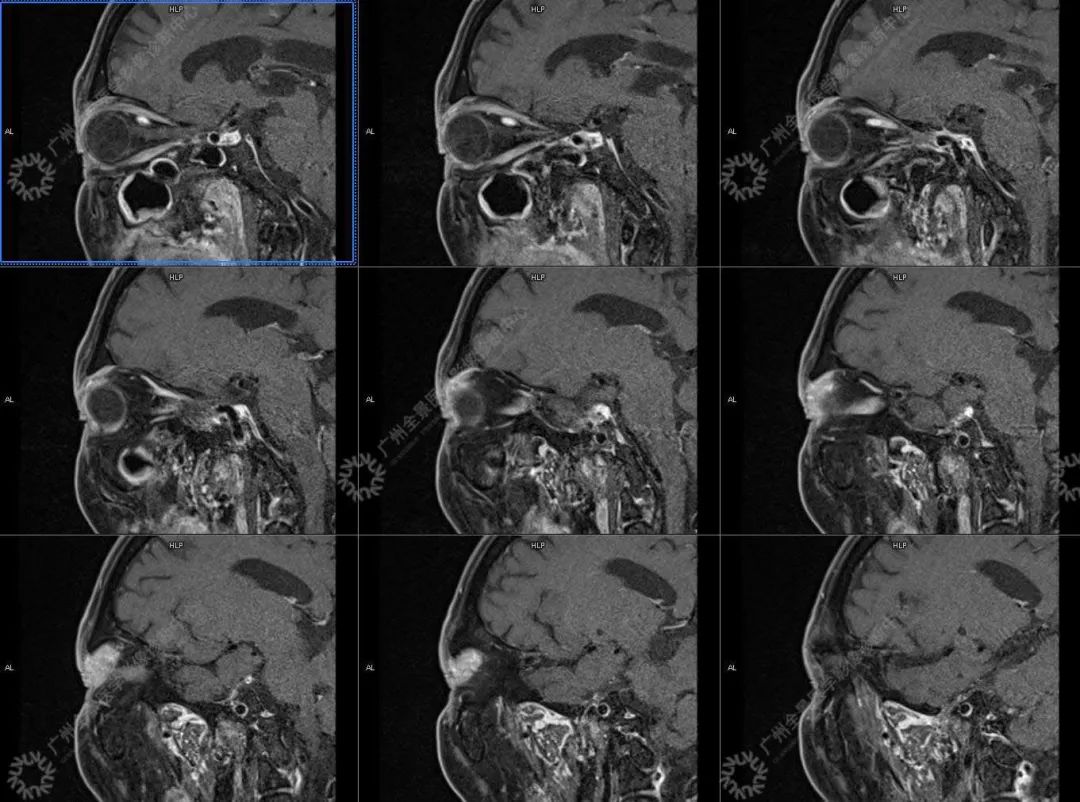

患者:男性, 71 岁

主诉:视力下降 2 年

现病史:双眼部隐痛、流泪,视力下降 2 年

结合影像及实验室检查,临床最终考虑 IgG4 相关性疾病。